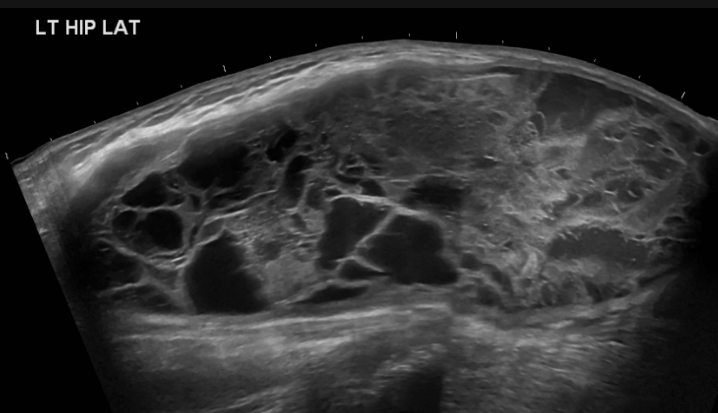

3. Organised haematoma